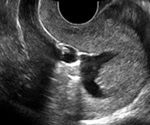

What is Sonohysterography?